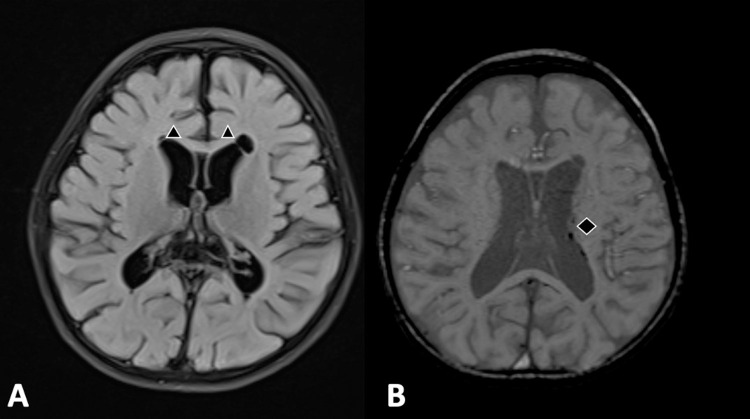

Negative regulator of reactive oxygen species (NRROS)-related microgliopathy (MIM# 618875) is a rare autosomal recessive neurodegenerative disorder. This case report describes a Saudi Arabian child with a novel homozygous NRROS variant, NM_198565.2: c.257T>C (p.Leu86Pro) presenting with drug-resistant epilepsy, rapid developmental regression, microcephaly, dystonia, and intracranial calcifications. Neuroimaging revealed bilateral intracranial calcifications, generalized brain volume loss, and connatal cysts; EEG showed a slow, suppressed background with multifocal epileptiform discharges. The variant is predicted to be deleterious by multiple in silico tools, suggesting a pathogenic effect on microglial function. This case underscores the importance of considering NRROS-related microgliopathy in children with early-onset neurodegeneration, drug-resistant epilepsy, and intracranial calcifications, enabling targeted genetic testing, diagnosis, and counseling.